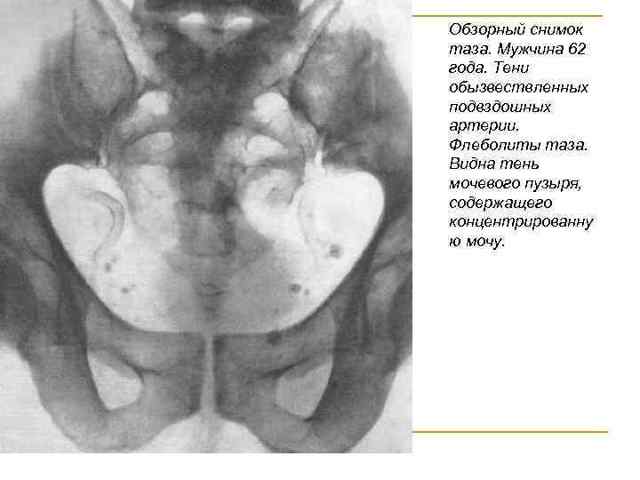

Флеболит это небольшие частички закальцинированных тромбов, которые образовываются в венах. На рентгеновских снимках проявляются в виде белых пятен.

- Рентген. Снимок позволяет определить точную локализацию камней. Они имеют овальную форму, характерную концентрацию.

У представителей мужского пола заболеваемость чаще обусловлена трудовой деятельностью (сидячая или тяжелая работа), а также наличием воспаления органов мочеполовой системы (простатит, цистит).

Кальциевые камни органов или вен малого таза наиболее часто обнаруживаются случайно на рентген-снимках в виде мелких камнеобразных уплотнений. Для определения точной локализации, а также размера образований проводят магнитно-резонансную или компьютерную томографию, позволяющую оценить их особенности в различных проекциях.

Венные камни у мужчин встречаются несколько реже, нежели у представительниц слабого пола, но их расположение не отличается от такового у женщин – нижние конечности, малый таз, селезеночная вена.

В венозных сплетениях малого таза флеболиты у мужчин появляются по причине варикозной болезни, связанной с сидячим образом жизни, наследственной предрасположенностью, а также при хронических воспалительных процессах мочеполовой сферы (простатит, цистит).

По данным некоторых авторов, на четверти всех рентгенограмм малого таза, сделанных по разным причинам, обнаруживаются тени флеболитов.

- Рентгенография определяет флеболиты в проекции малого таза в виде округлых теней с множеством слоев. Важным диагностическим признаком является наличие радиопрозрачного центра (симптом «хвоста кометы»).

- Рентгенография малого таза. На обзорных снимках рентгеноконтрастные флеболиты видны как овальные структуры с концентрическими кольцами («расслоениями»). Важными диагностическими признаками тазовых камней принято считать наличие радиопрозрачного центра, симптом «хвоста кометы».